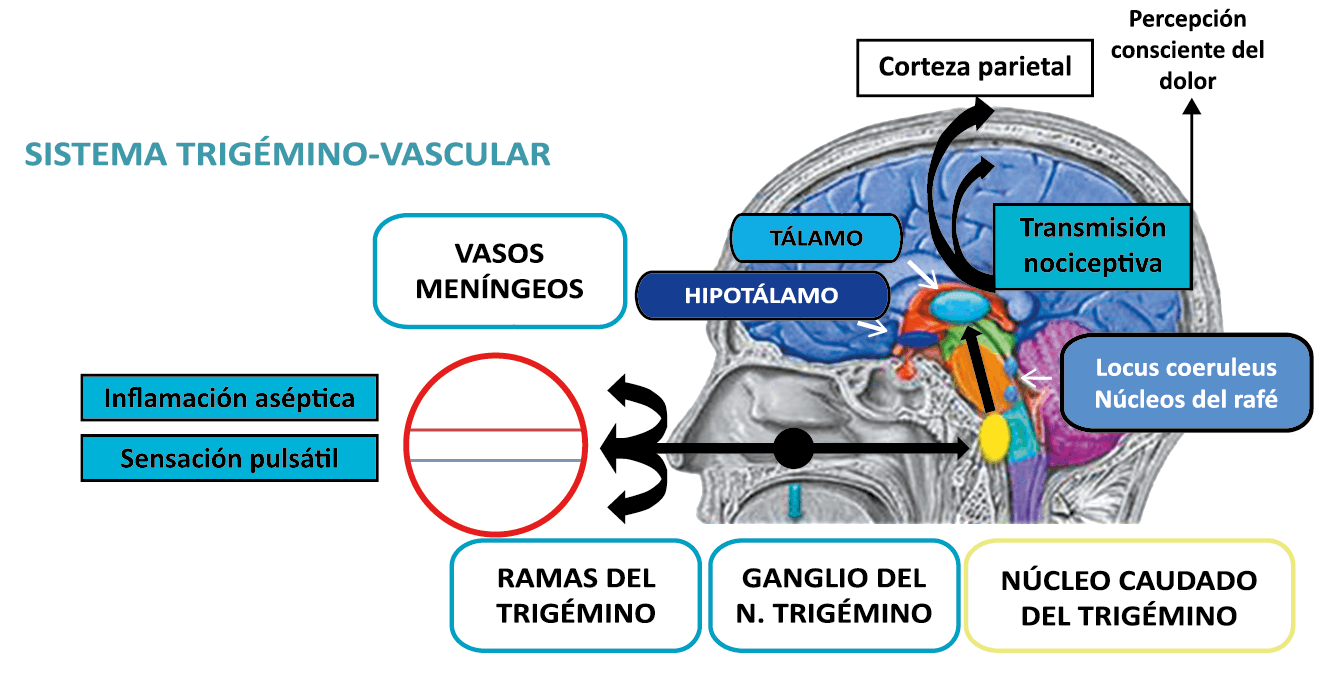

Todo lo mencionado contribuye al fenotipo del migrañoso y son vías que continuamente se están explorando para el desarrollo de nuevas terapias agudas y preventivas del dolor, más seguras y eficaces. Sin embargo, existe una controversia que gira en torno a dos cuestiones: la iniciación y el origen del dolor además de que todavía no se conoce el origen de los mecanismos neuronales que subyacen a la condición primaria en las personas susceptibles. Definitivamente la migraña implica la activación y sensibilización de las vías trigeminovasculares, así como el tronco cerebral y los núcleos diencefálicos(88). La vía aferente comienza en las aferentes vasculares nociceptivas de la duramadre que están para advertir, no para localizar. Su proyección al tálamo y la corteza y como se regula esta vía en cada nivel y por múltiples sistemas, ofrece la posibilidad de comprender los síntomas complejos y orientar las terapias. Los ataques comienzan como síntomas premonitorios, dificultad para concentrarse, bostezos, fluctuaciones del humor; y cambios homeostáticos, como la alimentación y el equilibrio de líquidos, que pueden incluir sensibilidades más generalizadas, como fotofobia y fonofobia. La fase premonitoria da paso a la fase de dolor con el sufrimiento acompañante y termina en una fase posdrómica de sentirse agotado por la experiencia. (Figura 1)

En la primera fase (figura 3), premonitoria, que precede a la cefalea, los sistemas del tronco encefálico y diencefálico modulan las señales aferentes, la fotofobia a la luz o la fonofobia al sonido, comienzan a disfuncionalizarse y eventualmente a evolucionar a la fase de dolor y con el tiempo a la fase de resolución o posdrómica. Aproximadamente en un tercio de los pacientes con migraña, sus ataques están asociados con déficits neurológicos, que incluyen perturbaciones corticales, denominadas colectivamente aura de migraña(3).

Un principio importante de esta teoría es que el desencadenante principal de la migraña proviene de la periferia, en los vasos sanguíneos de la duramadre, con la activación del sistema trigeminovascular proveniente del disparo de las neuronas trigeminales periféricas de primer orden en respuesta a una lesión nociceptiva o señales provenientes de las meninges que liberan mediadores neuroinflamatorios. La activación sostenida de las neuronas nociceptivas meníngeas durales provoca la activación secuencial y la sensibilización de las neuronas trigeminovasculares de primer orden (nociceptores periféricos), segundo orden (a nivel del TCC-complejo trigémino cervical) y tercer orden (trigeminotalámico), (Figura 5) así como la activación ascendente del cerebro, tallo y otras estructuras diencefálicas(97).

Se cree que esta activación secuencial explica la naturaleza pulsátil del dolor en la migraña, la hipersensibilidad sensorial nociceptiva, los síntomas neurológicos asociados que incluyen náuseas, vómitos, alteración de la alimentación y el sueño, así como la alteración cognitiva. Clínicamente, sin embargo, hay muchas lagunas. Los síntomas premonitorios en la migraña pueden estar presentes 24 a 48 h antes del dolor de cabeza y están representados por cambios en la activación en las regiones del cerebro medio e hipotalámico. Los desencadenantes de la migraña, como la privación de sueño y alimentos y el estrés, están bajo control homeostático.

El dolor de la migraña es, sin duda, una consecuencia de la activación o la percepción de la activación de los mecanismos neurovasculares, de allí que sea considerado un trastorno puramente neuronal. Mucha evidencia indica que los cerebros de las personas con migraña pueden ser diferentes en la forma en la cual responden a la estimulación sensorial, incluso interictalmente(102). Una hipótesis alternativa y que lo abarca todo es que el cerebro está en el centro del desencadenamiento de la migraña. Más que una activación secuencial de diferentes regiones del cerebro, la migraña es un trastorno del cerebro y por lo tanto, se considera un “estado cerebral”, que es una consecuencia de cambios o disfunciones en las regiones del tronco encefálico y el hipotálamo, que contribuyen a su vez a cambios a nivel celular y vascular en muchas regiones del cerebro. Esta hipótesis establece que la migraña puede describirse mejor como una consecuencia de la disfunción en el tronco encefálico y los núcleos hipotalámicos que normalmente modulan o activan las entradas sensoriales, como el tacto, la luz, los sonidos y los olores. Estos núcleos del tronco encefálico y del hipotálamo pueden considerarse “mediadores de la migraña” y su disfunción puede llevar al fracaso de los mecanismos de integración y filtrado cerebrales, lo que da como resultado la percepción de activación de los sistemas sensoriales en condiciones normales. La compleja red de conexiones entre las regiones del tronco encefálico, que incluyen PAG, RVM, locus ceruleus y SuS y los núcleos diencefálicos, incluidos el hipotálamo, el tálamo y la corteza, pueden conducir a la generación de síntomas a través de la misma disfunción central. La disfunción en estas regiones, a través del control descendente del tráfico nociceptivo trigeminovascular, puede conducir a la percepción del dolor de cabeza a través de la palpitación de los vasos normales y la disfunción continua puede conducir a la sensibilización central de las neuronas trigeminovasculares y la exacerbación del dolor con la actividad física normal, así como en la piel: alodinia cefálica y extracefálica. La convergencia de entradas sensoriales en el tálamo que se proyectan a la corteza puede explicar la hipersensibilidad a la luz, los sonidos y los olores. La misma disfunción puede conducir a cambios homeostáticos, controlados por el hipotálamo, relacionados con el sueño, la alimentación y la actividad. La alteración general de la función cortical y subcortical puede desencadenar eventos como el aura migrañosa y extenderse a una incapacidad general para funcionar correctamente. Los factores genéticos heredados juegan claramente un papel en la predisposición a la susceptibilidad a la migraña, al igual que el papel de los desencadenantes potenciales de la migraña, cuyo vínculo común parece jugar en el corazón de la homeostasis cerebral en el hipotálamo y el tronco encefálico. (figura 7).

El dolor de cabeza asociado con un ataque de migraña, puede incluir la región frontal, temporal, parietal, occipital y cervical alta, es consecuencia de la activación del sistema trigeminovascular. (Figura 10)

Por lo tanto, se cree que la naturaleza intensa y pulsátil del dolor en la migraña es el resultado de la activación, o la percepción de activación, de estas entradas nociceptivas de las estructuras intracraneales y extracraneales, que convergen y se transmiten a través del TCC. (Figura 17)

Toda la información nociceptiva de las estructuras craneovasculares se transmite a través del TCC y mediante conexiones ascendentes a otras áreas del tronco encefálico y el diencéfalo, involucradas en el procesamiento del dolor y otra información sensorial. La activación de la vía antes mencionada contribuye a la percepción del dolor durante la migraña y también a los síntomas autonómicos, endocrinos, cognitivos y afectivos que duran todo el episodio migrañoso.

El procesamiento del dolor es complejo y está mediado por una red de estructuras neuronales que incluyen la corteza cingulada, las ínsulas y el tálamo(28). El tálamo está en el corazón del procesamiento central y la integración de la información nociceptiva y se considera un centro de retransmisión para manejar la información sensorial entrante e incluso modularla. Se cree que la llamada “matriz del dolor”, que incluye el tálamo, así como las áreas somatosensoriales primarias (S1) y secundarias (S2), la corteza cingulada anterior (CCA) y la corteza prefrontal, está involucrada en la integración de todos los sentidos, respuestas afectivas y cognitivas al dolor y se activan durante el procesamiento nociceptivo(28). (Figura 18)

Siendo el tálamo el centro principal para el procesamiento de la información nociceptiva sensorial en el cerebro, la transmisión de esta información para su procesamiento en las estructuras corticales donde los individuos la perciben es un factor clave. (Figura 18) Los tratamientos agudos como los “triptanos” (agonistas de los receptores 5-HT1B/1D)(29) y los antagonistas de los receptores CGRP(30) pueden inhibir las entradas nociceptivas durales agudas. Del mismo modo, los preventivos de la migraña propranolol(31), valproato de sodio(32) y topiramato(33)también pueden inhibir las entradas trigeminotalámicas nociceptivas durales en el VPM (Núcleo ventral posteromedial).